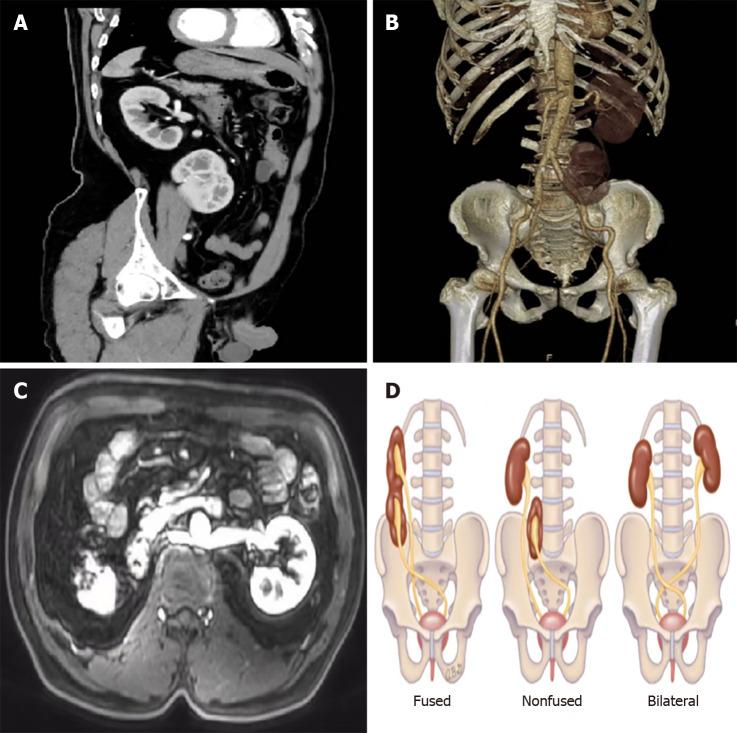

Crossed renal ectopia (CRE) occurs when one kidney crosses the midline from the primary side to the contralateral side while the ureter remains on the primary side. Rectal cancer, one of the most common malignant tumors of the digestive tract, refers to cancer from the dentate line to the rectosigmoid junction. The concurrent presentation of CRE alongside rectal cancer is an uncommon clinical observation.

Herein, we report a 69-year-old male patient with rectal cancer who was diagnosed with CRE computed tomography during hospitalization. Following thorough preoperative evaluations, the patient underwent Dixon surgery.

We performed laparoscopic radical resection of rectal cancer and adequate lymph node removal in a patient with CRE with no postoperative discomfort.

交叉异位肾(CRE)是指一侧肾脏越过中线从原侧移至对侧,而输尿管仍位于原侧。直肠癌是消化道最常见的恶性肿瘤之一,是指从齿状线至直肠乙状结肠交界处的癌症。CRE与直肠癌同时出现是一种罕见的临床现象。

在此,我们报告一名69岁的直肠癌男性患者,其在住院期间通过计算机断层扫描被诊断为CRE。经过全面的术前评估后,该患者接受了 Dixon 手术。

我们对一名患有CRE的患者进行了腹腔镜直肠癌根治性切除术及充分的淋巴结清扫,术后患者无不适。